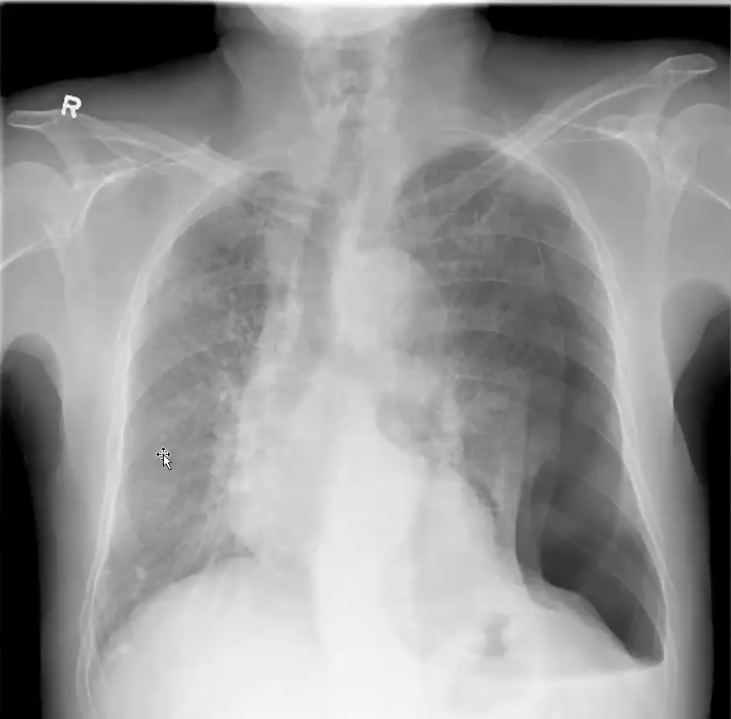

What’s your diagnosis?

Right lower lobe pneumonia because you have a right heart border (no silouhette sign) and a spine sign